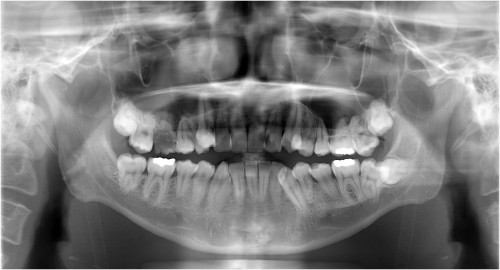

術前

インプラント挿入

土台装着

被せ物装着

同パノラマ写真

被せ物装着後歯肉の盛り上がり